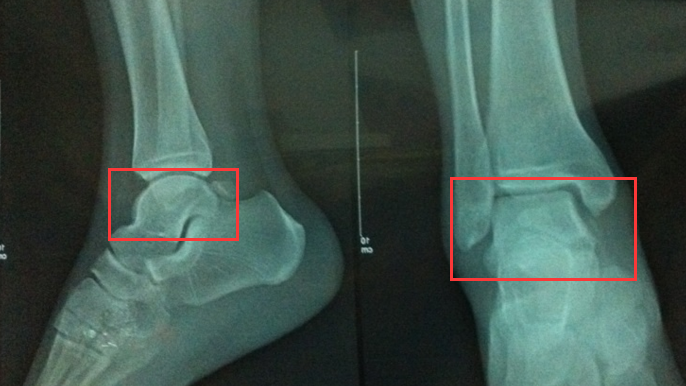

2011 年,当时我在厦大读研,我的右脚不慎在一场篮球赛上踩在了猪队友的脚上,我当时都能听到脚踝处 “咔嚓” 一声。。。

同学们立马把我送到厦大兽医院(厦大医院。。。我们都这么叫它),花 7 块钱拍了个 X 光(话说也是真心便宜,不知道现在涨价了没),X 光显示骨头一切正常,于是众人打道回府。

但我一直觉得不对劲,首先,我的脚肿得太厉害了!脚踝足足粗了一倍还多,而且特别痛,那绝对不是普通扭伤的疼痛程度,我头两天晚上甚至睡不着觉。第四天,我的脚依旧钻心地疼痛,虽然 X 光显示骨头没问题,但我依旧心有忐忑,于是我再次来到厦大兽医院,找到了之前的那个医生。

到中山医院预约好 MRI,四天后做出来的结果是:距骨挫伤!

骨挫伤本身不是特别大的问题,毕竟骨头没断,但距骨挫伤绝对是比普通骨折要严重许多的问题。距骨是脚踝上的那个圆圆的骨头,说白了,人能运动靠的就是距骨这两个轴承。人身上两个骨头比较容易坏死,股骨头、以及距骨。

(圆圆的那个 “轴承” 就是距骨,一旦受伤,这块骨头是人身上所有骨头中最难恢复的,没有之一!因为它的职责就是承重,即便恢复了,也要继续被“压迫”,因为很难痊愈,其一旦物理结构被破坏,以现在的医学条件来说 100% 痊愈很困难)